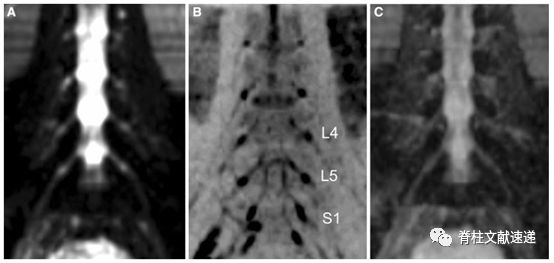

图注:健康志愿者腰椎神经根冠状扩散加权图像(DWI)。L4、L5和S1表示腰4、5骶1神经根。C图是基于DWI计算得到的ADC图。